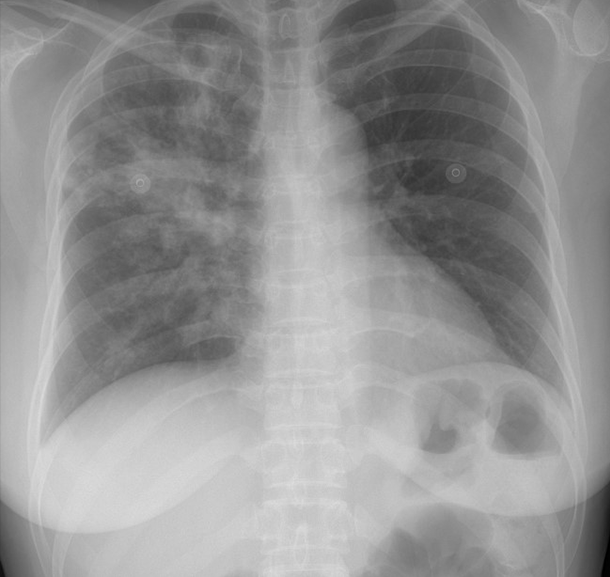

환자의 임상 증상 문진과 진찰 후, 흉부 X선 검사 및 흉부 CT가 진단에 도움이 됩니다.

• 폐결핵 비결핵성항상균 폐질환

img img

그림: 폐결핵과 비결핵성항산균 폐질환의 흉부엑스레이 사진과 흉부전산화단층활영 사진

비결핵성항산균 폐질환은 폐결핵과 비교하였을 때 서서히 진행하거나 변하지 않을 수 있으며, 만성적인 경과를 보이고, 진단이 늦어지는 경향이 있습니다. 두 질환은 모두 환자의 객담을 통한 객담 항산균 도말검사, 객담 항산균 배양 검사를 진행합니다. 객담 배양이 되기 전에는 객담 도말 검사 양성 소견만으로는 결핵균과 비결핵성항산균이 구별이 되지 않으며, 구별을 위해서 결핵균 핵산증폭검사(TB-PCR) 검사를 시행합니다.